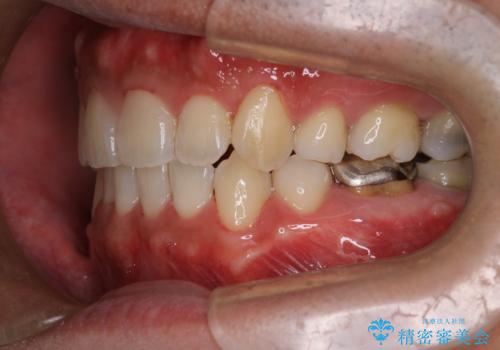

初診時の歯並びの状態としては、右上の犬歯がいわゆる八重歯の状態であり、強いガタガタが上下ともにある状態でした。

スペースの不足量が多く、抜歯を伴うワイヤー矯正にて治療を行いました。

若干の口元の突出感もあったため、抜歯によるスペースを利用し、がたつきの改善と前歯の後退をを行いました。